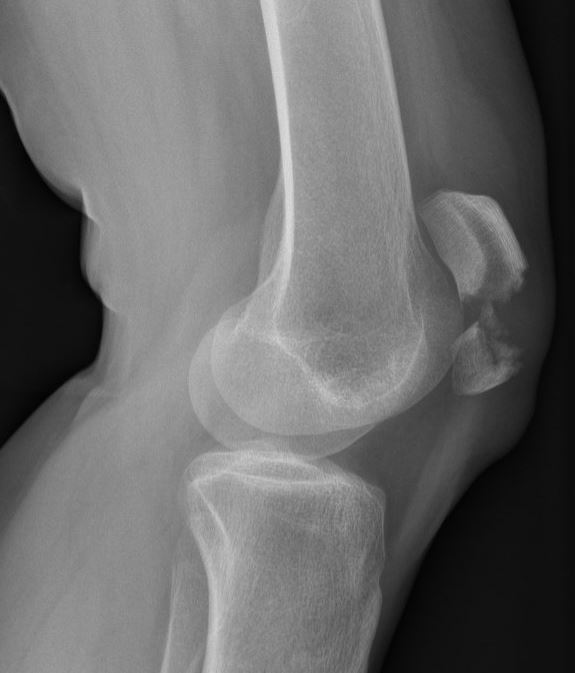

Een breuk van de knieschijf ontstaat meestal door een val direct op de knieschijf of door een harde klap tegen de knieschijf, bijvoorbeeld ten gevolge van een verkeersongeval. Bij een breuk van de knieschijf is er vaak direct pijn en zwelling ter hoogte van de knie. Daarnaast is er vaak een onvermogen om de knie te strekken, omdat de pees van de quadriceps niet meer in verbinding staat met het onderbeen. Een Röntgenfoto kan de diagnose bevestigen.

Meestal als de knieschijf breekt gaan de breukdelen uit elkaar staan en zal daarmee het strekmechanisme van de knie uitvallen. Bovendien zal de achterkant van de knieschijf niet meer egaal zijn en daarmee het gewrichtsoppervlak met het dijbeen verstoord zijn. In dat geval moet dit operatief hersteld worden.